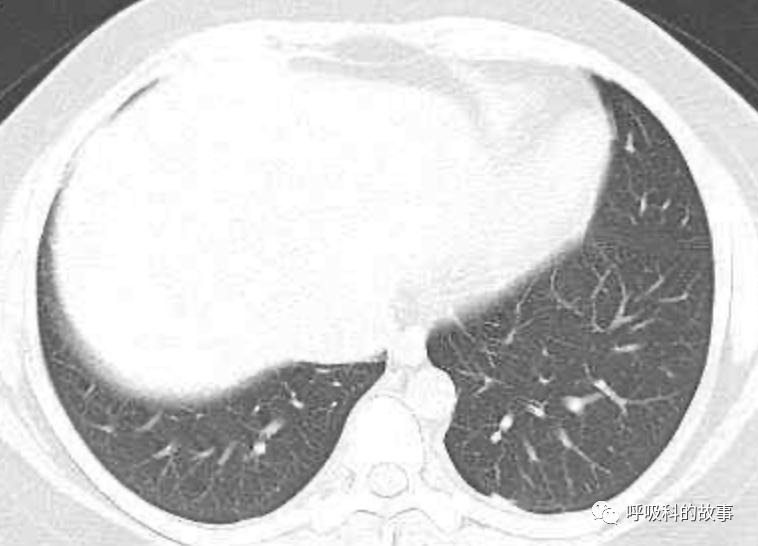

患者发热后行胸部CT检查(6月21日,住院第13天),可见两下肺有条片影,当时考虑是肺炎引起的发热。